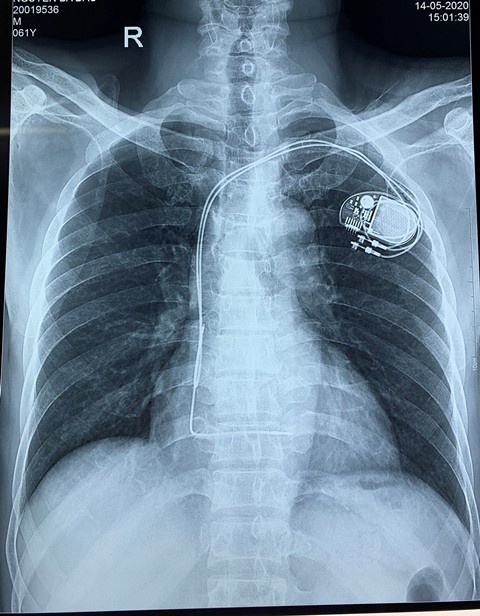

Máy tạo nhịp tim vĩnh viễn trong cơ thể bệnh nhân. Ảnh: BVCC.

Ông D. có chỉ định phẫu thuật cấp cứu, tuy nhiên, tình trạng bệnh lý tim mạch nặng, phức tạp, tiên lượng có thể ngừng tim ngay khi gây mê hồi sức trong và sau mổ. Lãnh đạo bệnh viện đã chỉ đạo hội chẩn chuyên khoa gồm Cấp cứu, Gây mê hồi sức, Tim mạch, Ngoại tiêu hóa, quyết định đặt máy tạo nhịp tim tạm thời cho bệnh nhân trước khi phẫu thuật.

Sau đó, kíp can thiệp tim mạch do các bác sĩ khoa Tim mạch - Lão học đặt máy tạo nhịp tim tạm thời cho bệnh nhân, đảm bảo ca mổ cấp cứu được diễn ra an toàn.

Qua hội chẩn, các bác sĩ xác định đã đặt máy tạo nhịp tim vĩnh viễn để đảm bảo bệnh nhân không bị nhịp chậm, tiến tới ổn định nhịp tim và làm giảm tiến triển suy tim, giảm nguy cơ đột tử.

Ngay sau đặt máy, các thông số kỹ thuật của máy ổn định, sức khỏe của bệnh nhân tiến triển tốt, các chỉ số đều ở mức bình thường ghi nhận nhịp máy tạo nhịp là >60 lần/phút. Dự kiến, bệnh nhân sẽ được xuất viện trong vài ngày tới.